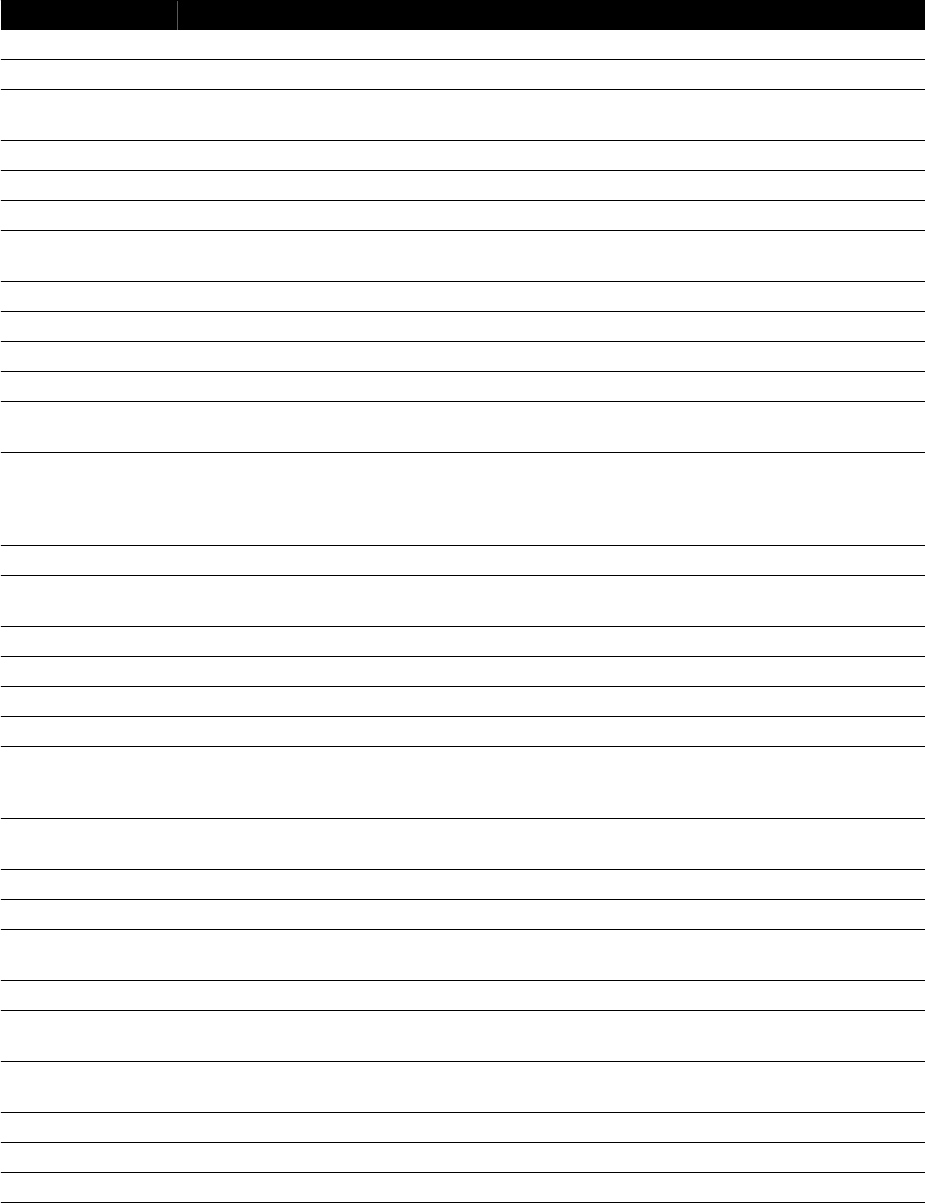

11.17 Narzędzie laserowe XperGuide (opcja)................................................................................ 203

11.17.1 Włączanie i wyłączanie narzędzia laserowego XperGuide................................... 204

16.13.1 Narzędzie laserowe XperGuide............................................................................ 286